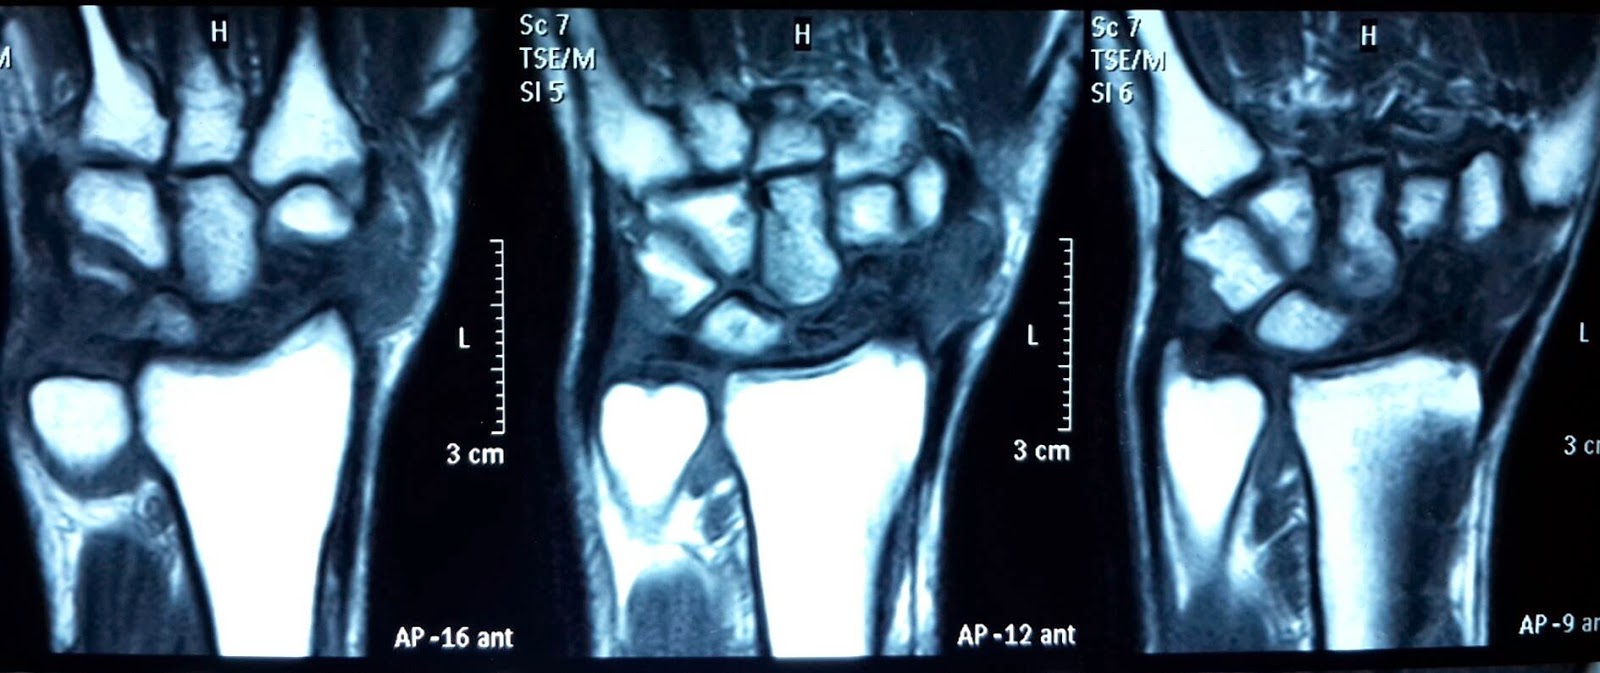

Discusión entre pares_25 years male patient with neglected fracture left scaphoid with AVN the patient is right handed and he is a manual worker…. enero 20, 2015 por victor valdes https://www.facebook.com/groups/indian.ortho/ Zaky Basuony 5 horas 25 ys male patient with neglected fracture left scaphoid with AVN the patient is right handed and he is a manual worker….your opinion Mahmoud Ibrahim Kandil four corner fusion 4 horas · Me gusta · 1 Srinivas Daravathu http://www.orthobullets.com/…/snac-scaphoid-nonunion… SNAC (Scaphoid Nonunion Advanced Collapse) – Hand – Orthobullets.com ORTHOBULLETS.COM 4 horas · Me gusta · 1 Srinivas Daravathu Dr Kir Pat sir ,ur opinion pls 4 horas · Me gusta Kir Pat Scaphoid excision,four quadrant fusion 2 horas · Me gusta · 1 P Rajasekhar Rao capitiate shortening and fusion 1 hora · Me gusta Israr Ahmad Excision of proximal pole. .. choice of arthrodesis depends on symptomatology 20 min · Me gusta